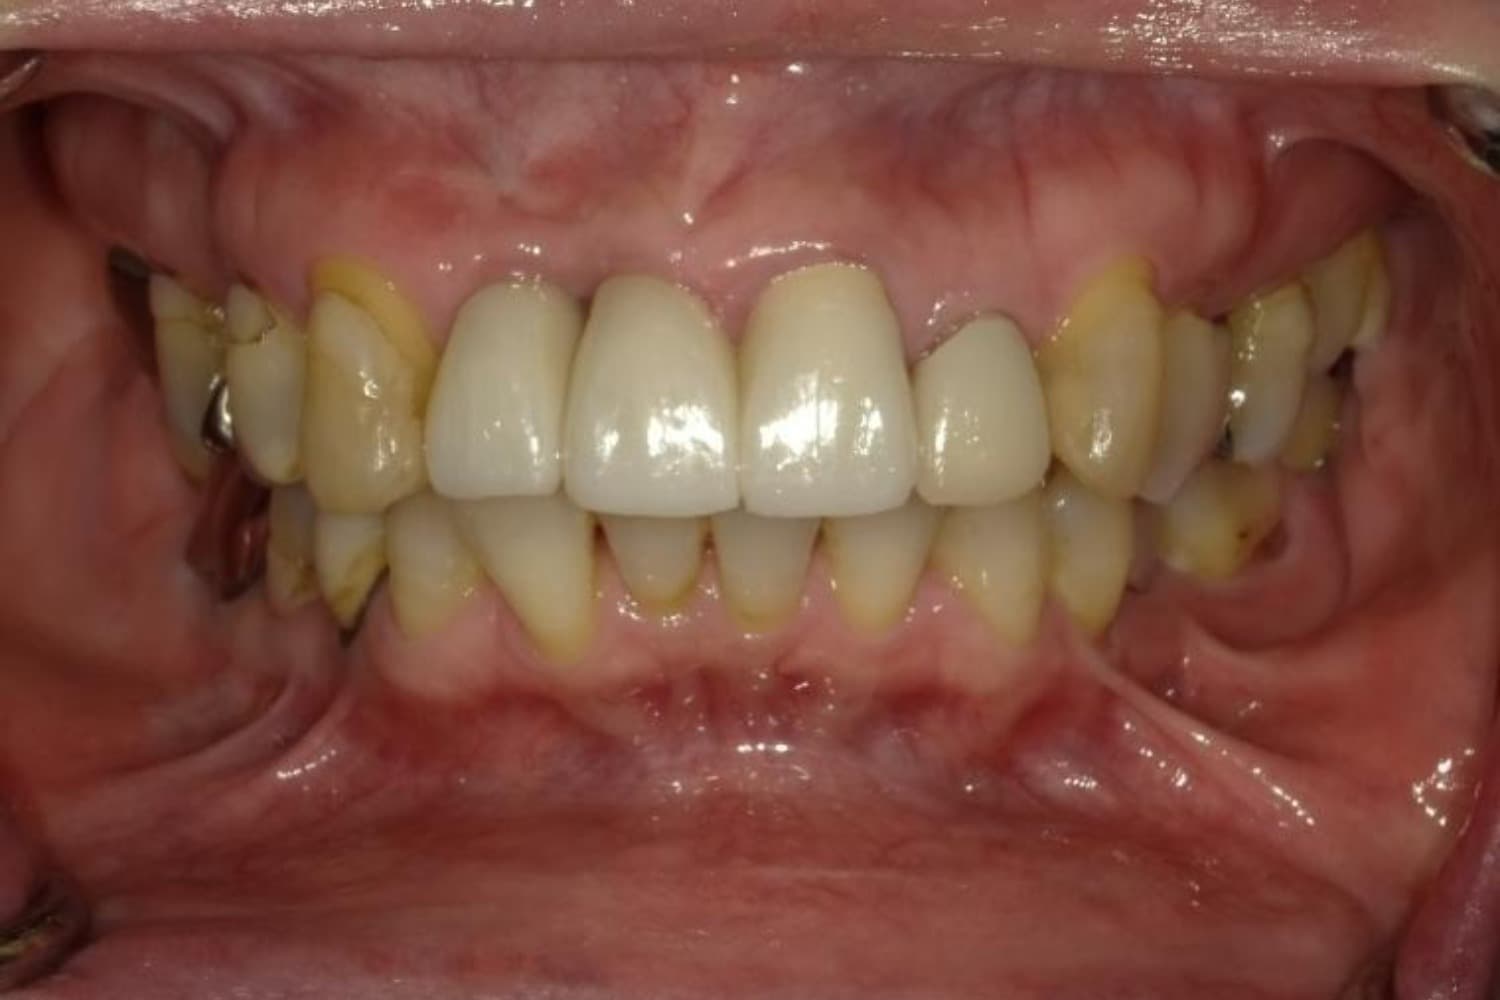

上顎前歯2本欠損症例(2)

Before

After

保存が困難な状態であったため抜歯をおこない、その後インプラントを2本埋入しました。

年齢

67歳

性別

女性

主訴

右上前歯は以前に別の医院で治療中でしたが中断されたため、当院へご相談くださいました。

治療期間

10ヵ月

費用

120万円

副作用・リスク

インプラント治療は外科的な処置を伴い、多少の腫れや痛みが出ることがあります。 多くの場合は鎮痛薬で和らげることができます。